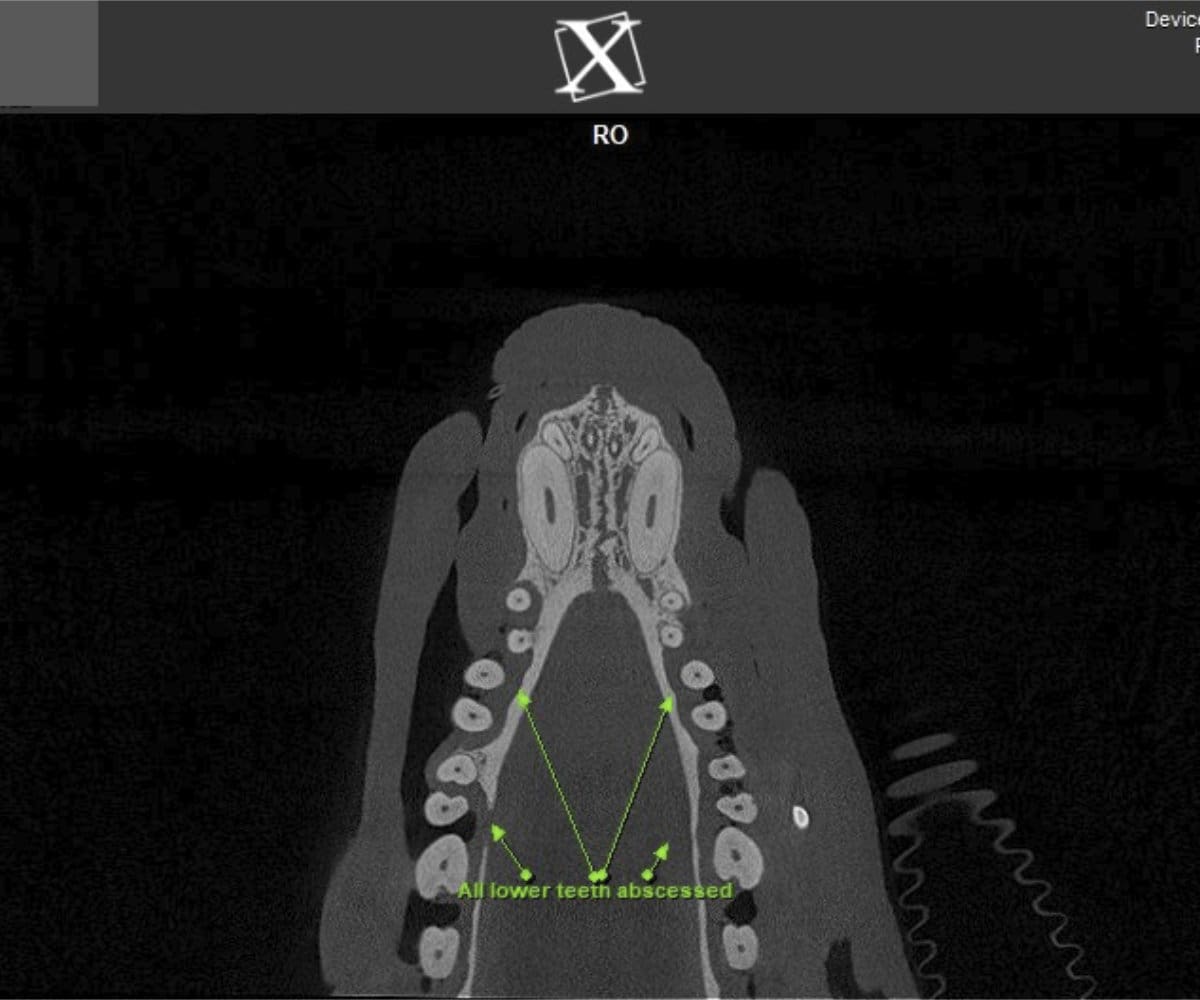

In addressing these limitations, CBCT emerges as a pivotal advancement. Conducting a CBCT scan on our patients is characterized by minimal time and effort, effectively reducing anesthesia duration. Moreover, this technology facilitates the generation of a comprehensive 3D reconstruction of the teeth and skull, surpassing the constraints of traditional radiographs. This innovative approach empowers our veterinary professionals to identify oral pathologies that may have been missed on traditional radiographs.

Cone beam CT technology provides veterinarians with 3-dimensional images in far greater detail than dental radiographs. CBCT scans significantly decrease the amount of time a patient spends under anesthesia compared to the time it takes to complete dental radiographs.

Our CBCT VetCAT unit is easily rolled up to our treatment table and takes only 40 seconds to complete a scan. It has proven to be invaluable in the diagnosis and treatment planning for pets with periodontal, endodontic and cancerous disease conditions. It is also indispensable in the evaluating our trauma cases with jaw fractures.